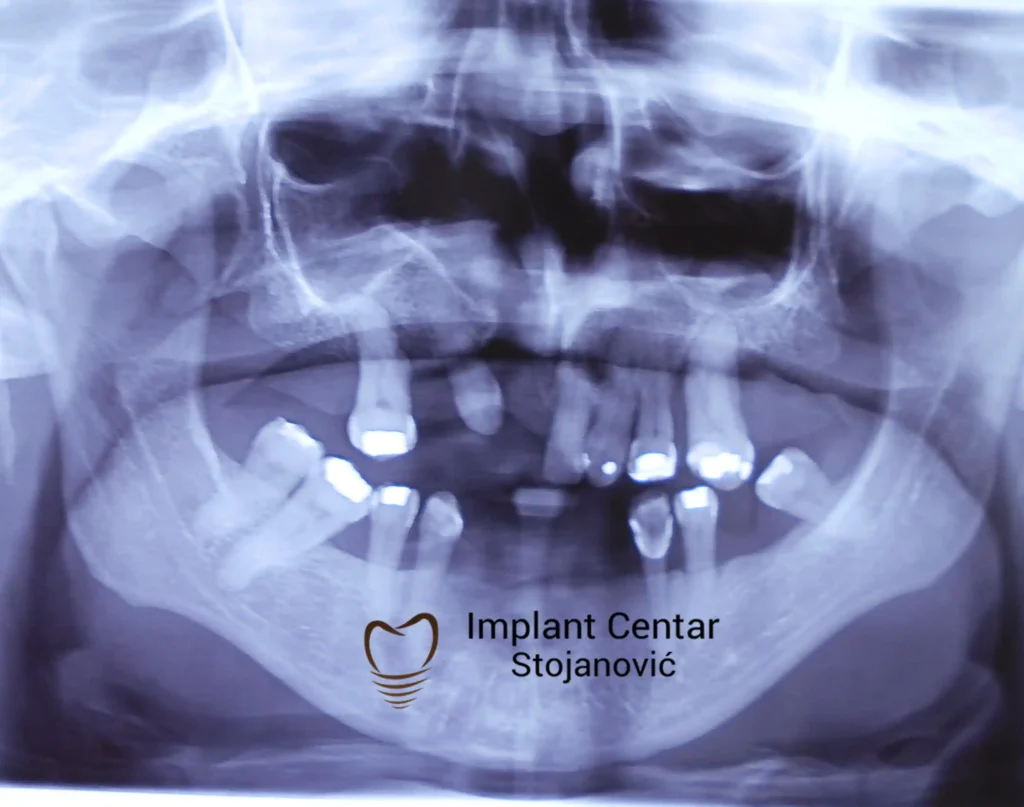

Na slici 1. i slici 2. prikazan je izgled pacijenta pre početka terapije – klinički i rendgenološki.

Nakon vađenja zuba, ugrađeni su implantati. Na slici 3 prikazan je ortopan snimak sa ugrđenim implantatima. Tokom perioda osteointegracije, pacijent je bio zbrinut fiksnim privremenim krunicama na implantatima, koje su izrađene samo dva dana nakon hirurške intervencije.